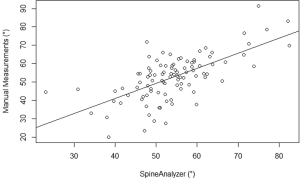

The mean kyphosis angle between the superior endplate of Th5 and the inferior endplate of Th12 of the sample as determined by the SpineAnalyzer® software measurements was 53° with a standard deviation of 10° and the mean kyphosis angle by manual measurements was 54° with a standard deviation of 12°. The Pearson’s correlation coefficient r between the manual measurements and the calculations derived from the SpineAnalyzer® software was 0.65 [95% confidence interval (CI): 0.53-0.75; P=2×10–13] (Figure 3). There was a substantial intraclass correlation with a coefficient of 0.64 for both consistency and absolute agreement (95% CI: 0.51-0.74 P=5×10–13 and P=4×10–13, respectively). The mean difference between methods was 1° (95% CI: –2°-4°) and not different from 0 (P=0.4). The interval between the 95% limits of agreement was –20°-17° where approximately half the individuals (47%) showed a difference of less than 5° and about three quarters less than 10° between the techniques (76%). The Bland-Altman plot did not show systematic biases of proportional error, dependency of variation on the magnitude of measurements, extreme outliers, systematic under- or overestimation (Figure 4).